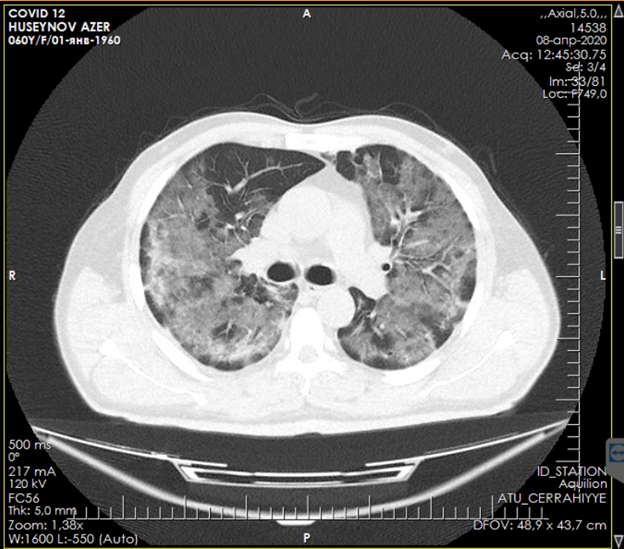

Figure 2. CT scan of the lungs upon admission

Figure 4. CT scan after patient improvement

Figure 5. CT scan of the lungs after improvement

Non-invasive ventilation was carried out by an oral-nasal mask with a ventilator ELISA. Installation and adjustment of the parameters was carried out according to the general condition and according to the data of blood gases: respiratory rate <35, pH> 7.30, neurological dysfunction according to the Kelly scale> 3-5, a modified scale for determining the participation of auxiliary respiratory muscles <3 points. For hypercapnia, the following parameters were set: Ps - 12, PEEP - 5 cm water column, FiO2 -30-40%, and with hypoxemia - Ps - 12, PEEP - 5 cm water column, FiO2 -50-60 %. The median treatment period with NIV was 6 days. The average daily treatment time with NIV on the first day was 17.3 hours, on the second day - 18.2 hours and on the third day 16.7 hours. The patient was discharged on the 12th day with improvement.